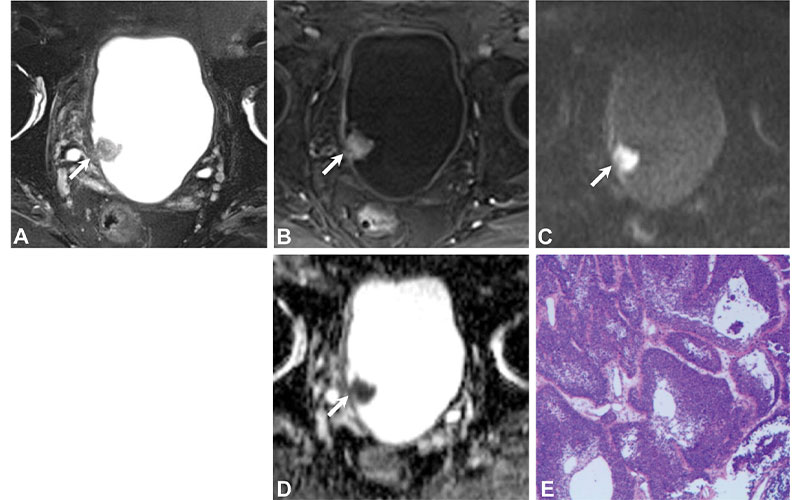

In this retrospective study, patients with histopathologically confirmed bladder cancer occurring at the ureteral orifice were analyzed. Two blinded radiologists independently scored multiparametric MRI scans according to VI-RADS.

A total of 78 patients were included in the final analysis: 25 with NMIBCa and 53 with MIBCa. At consensus reading, one case (1%) was scored as VI-RADS 1, 27 cases (35%) were scored as VI-RADS 2, six (8%) were scored as VI-RADS 3, 10 (13%) were scored as VI-RADS 4, and 34 (44%) were scored as VI-RADS 5.

On comparison of the VI-RADS score with histopathologic findings, it was confirmed that the presence of muscle invasion was 0% (zero of one) for VI-RADS 1, 15% (four of 27) for VI-RADS 2, 83% (five of six) for VI-RADS 3, 100% (10 of 10) for VI-RADS 4, and 100% (34 of 34) for VI-RADS 5. The area under the receiver operating characteristic curve (AUC) of VI-RADS in the detection of MIBCa was 0.96, indicating a high diagnostic test accuracy.